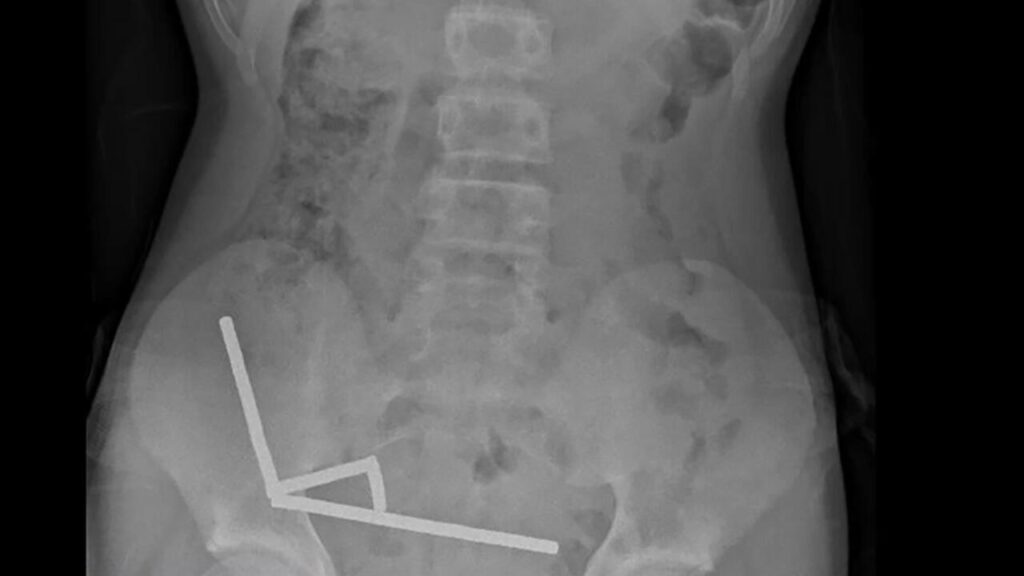

Kiderült, hogy a mágnesek vonzásának törvénye a belekben is működik, össze is álltak négy oszlopba. Ez nem természetes biológiai folyamat, négy napig szenvedett a fiú, mielőtt kórházba került, ahol kiderült, hogy a mágnesek nyomása szövetelhalást okozott a vékony- és vastagbelekben. Az orvosok az elhalt részeket és a mágneseket is eltávolították.